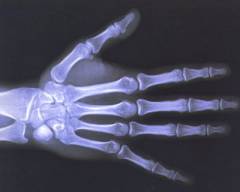

Давайте вначале попробуем понять разницу между организмом взрослого человека и ребенка, а затем разобраться, как рентгеновское излучение может повлиять на обоих. Рентгеновские лучи – электромагнитные волны с высокой энергией – обладают свойством проникать сквозь наименее плотные ткани организма, и задерживаться более плотными, давая изображение их контуров – это их свойство нашло широкое применение в современной радио- и рентгенодиагностике.

Однозначного ответа на этот вопрос нет. Рентгеновское исследование показано в случае возникновения экстренных ситуаций, когда без его проведения вероятность тяжелых осложнений или даже гибели матери чрезвычайно высока. Кроме того, при переломах костей конечностей, например, рентгенодиагностика проводится одновременно с тщательным экранированием (наложением специальных защитных кожухов, фартуков, накладок на область таза, живота и груди).

К тому же при рентгене головы или конечностей облучение практически не действует на живот матери. Надежной защитой являются фартук, оберегающий плод от рентгеновских лучей.

Рентгенографическое исследование — ценная диагностическая процедура, которая помогает визуализировать органы и ткани неинвазивным способом (посредством проникновения лучей через тело человека).